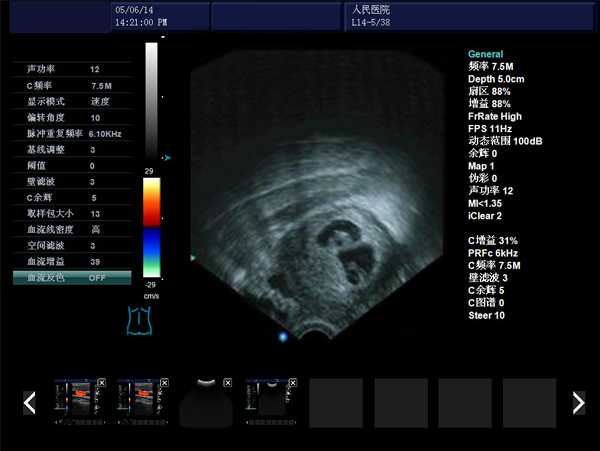

DW-480全數字超聲婦產科手術監視儀

DW-480

產品性能

高集成數字式

寬頻探頭,頻率范圍從2.0MHz到10.0MHz

強勁的組合式模塊化軟件設計

全數字式大容量圖像存貯和文件歸檔管理

操作系統簡單靈活

探頭與陰道窺器相結合,不進入宮腔,不占手術宮頸空間,手術更方便

實時動態高線密度超大角度掃描,有效提升橫向分辨力和側向分辨力、圖像自然更清晰

采用大容量電影回放,實時精微顯示等全數字圖像處理技術,宮腔內部圖像清晰可辨,不容錯過一點殘留,手術干凈徹底,避免了吸宮不全、漏吸等并發癥的發生